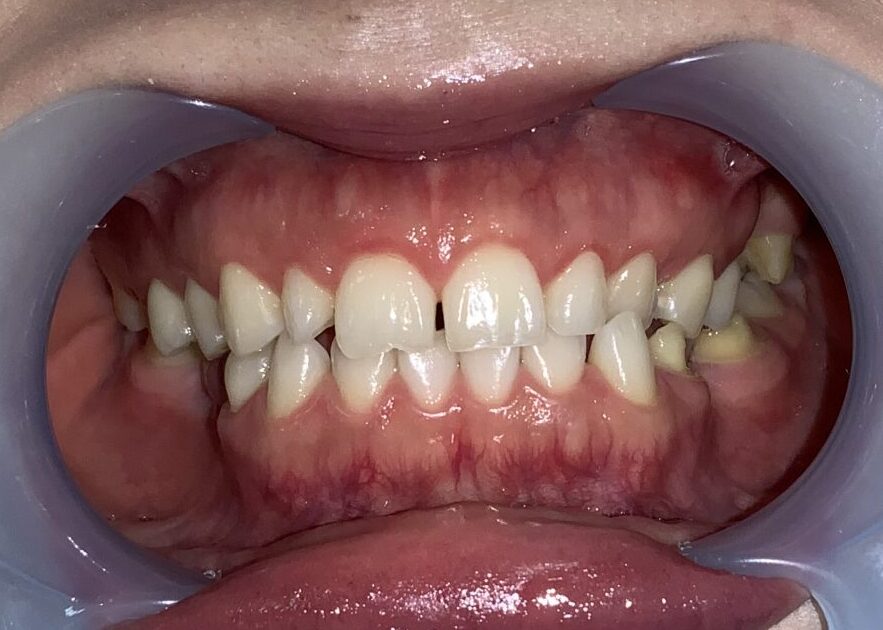

全ての歯の手術を終えて終了です。

こんなに歯が大きくなり、歯ぐきが小さくなり、ガミースマイルも改善しました。

笑った時に歯ぐきが丸見えの状態は改善されました。